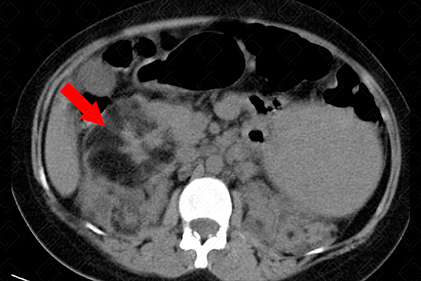

Descrição das figuras: Rins tópicos, de volume aumentado, às custas de múltiplas formações nodulares, algumas espontaneamente densas e outras com densidade de gordura, distribuídas difusamente pelo parênquima renal, bilateralmente, devendo representar cistos (setas amarelas). Destaca-se formação nodular heterogênea, com densidade predominante de gordura, no polo superior do rim direito, medindo 8,3 x 7,6 cm, compatível com angiomiolipoma (seta vermelha) Moderada esplenomegalia heterogênea, medindo 15,3 cm, às custas de pequenas formações hipodensas, devendo representar hamartomas (setas azuis). Considerar, dentre as hipóteses diagnósticas, esclerose tuberosa como a mais provável para as alterações descritas acima.

• Renais: O acometimento renal e o neurológico são as principais causas de morbimortalidade associadas a esclerose tuberosa. O mais característico são os angiomiolipomas renais (tumores renais benignos), sendo observados em cerca de 80% dos pacientes com esclerose tuberosa. Eles crescem progressivamente ao longo dos anos, com seu pico na adolescência. Estes pacientes apresentam ainda cistos renais múltiplos, hipertensão arterial, pielonefrite e doença renal progressiva. Além disso, há relatos de maior incidência de carcinoma de células renais.